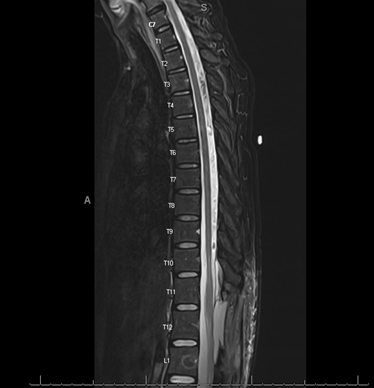

The patient is a 42-year-old female with no pertinent past medical history who presents to neurosurgery spine clinic citing chronic back pain and muscle spasms after failure of conservative treatment including physical therapy, epidural steroid injections, and medications. The patient underwent preoperative imaging using CT and MRI and was diagnosed with a 7.1 cm extradural arachnoid cyst at T11 to L1; Preoperative MRI displayed in figures 1-3 below. This extradural arachnoid cyst was causing compression of the cord and resulting in severe and worsening thoracic back pain and bilateral lower-extremity symptoms including pain, numbness, and loss of balance. The patient was positioned in a lateral decubitus position, lumbar region prepped with chlorhexidine then draped in usual sterile fashion. Lumbar drain was placed, clear CSF obtained, 0.2cc fluorescein in 10cc sterile saline was injected then the lumbar drain was secured with Ioban.

Figure 3: Axial T1 weighted MRI from top of superior endplate at T11.